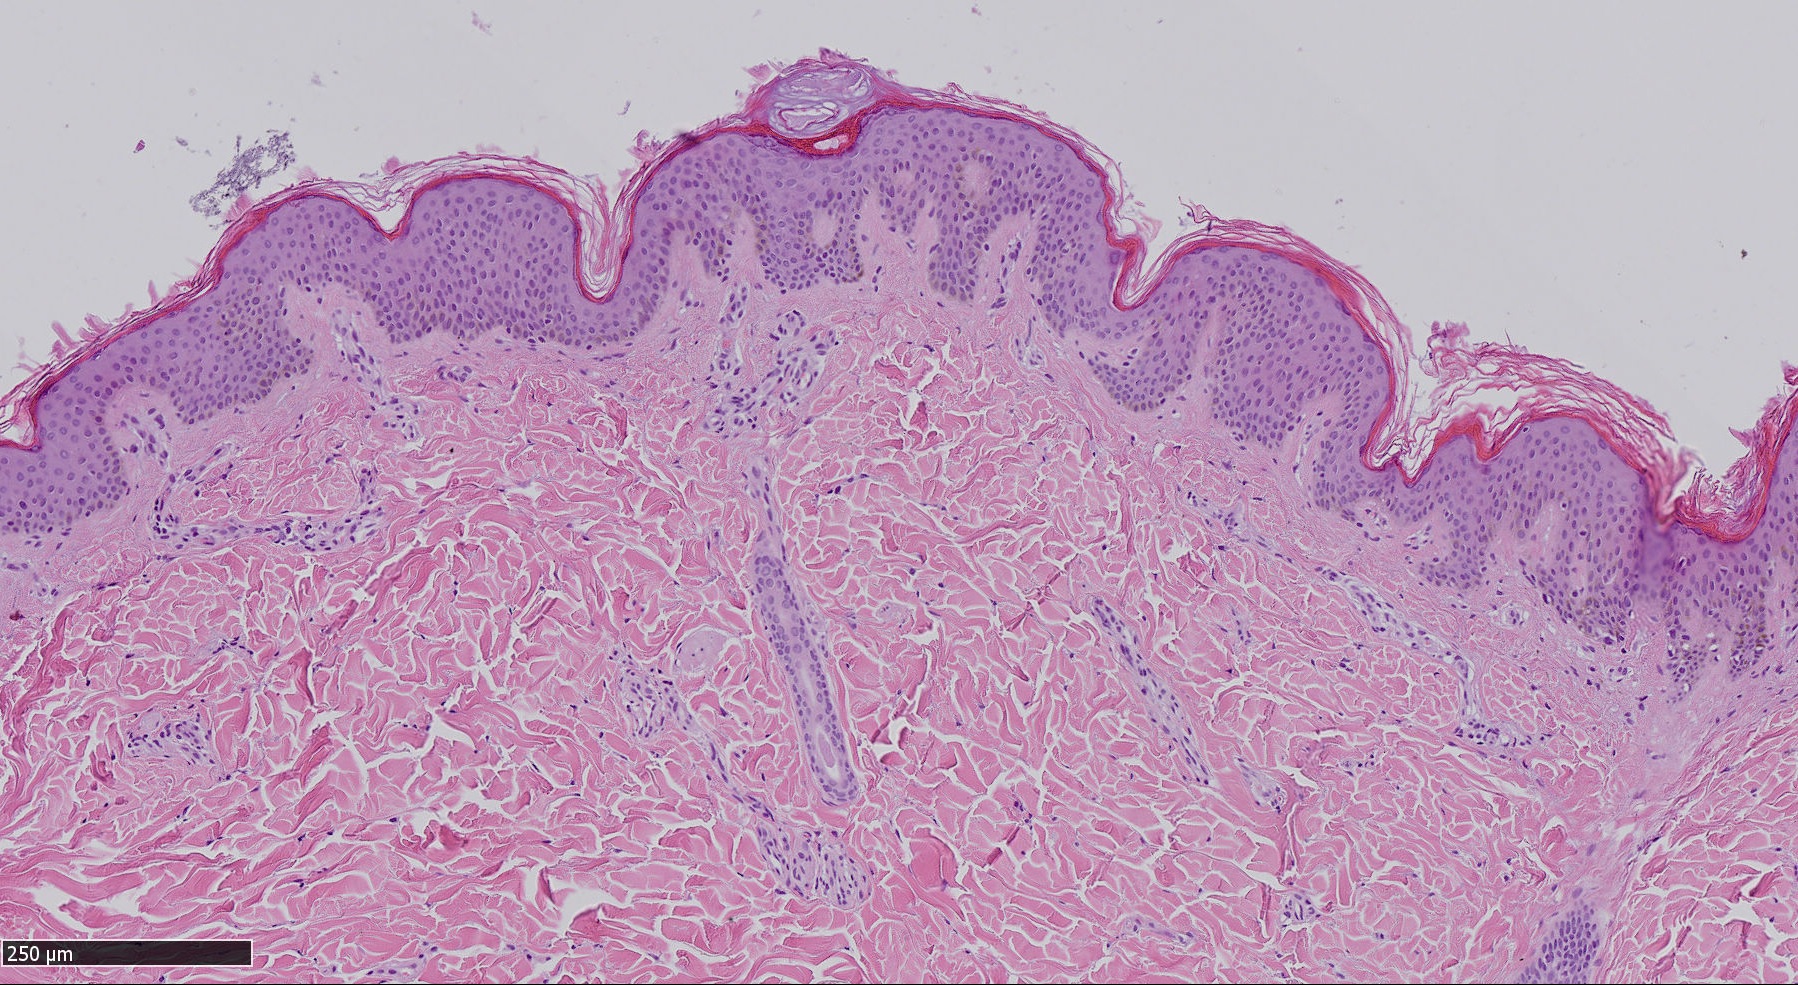

Contro il melanoma la giusta sequenza di immunoterapia e terapia molecolare

I pazienti con melanoma avanzato e che presentano una mutazione del gene Braf possono ottenere un beneficio clinico dalla combinazione di due trattamenti: l’immunoterapia seguita dalla terapia molecolare con inibitori del gene Braf mutato. È quanto emerge dallo studio internazionale Secombit (Sequential Combo Immuno and Target therapy study), i cui risultati sono stati pubblicati il 1 settembre sulla prestigiosa rivista internazionale di oncologia Journal of Clinical Oncology e, dal 9 al 13 settembre, saranno presentati al congresso European Society of Medical Oncology in programma a Parigi.